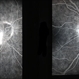

- Fundus fluorescein angiogram of a patient with arteritic anterior ischemic optic neuropathy and choroidal ischemia associated with giant cell arteritis.